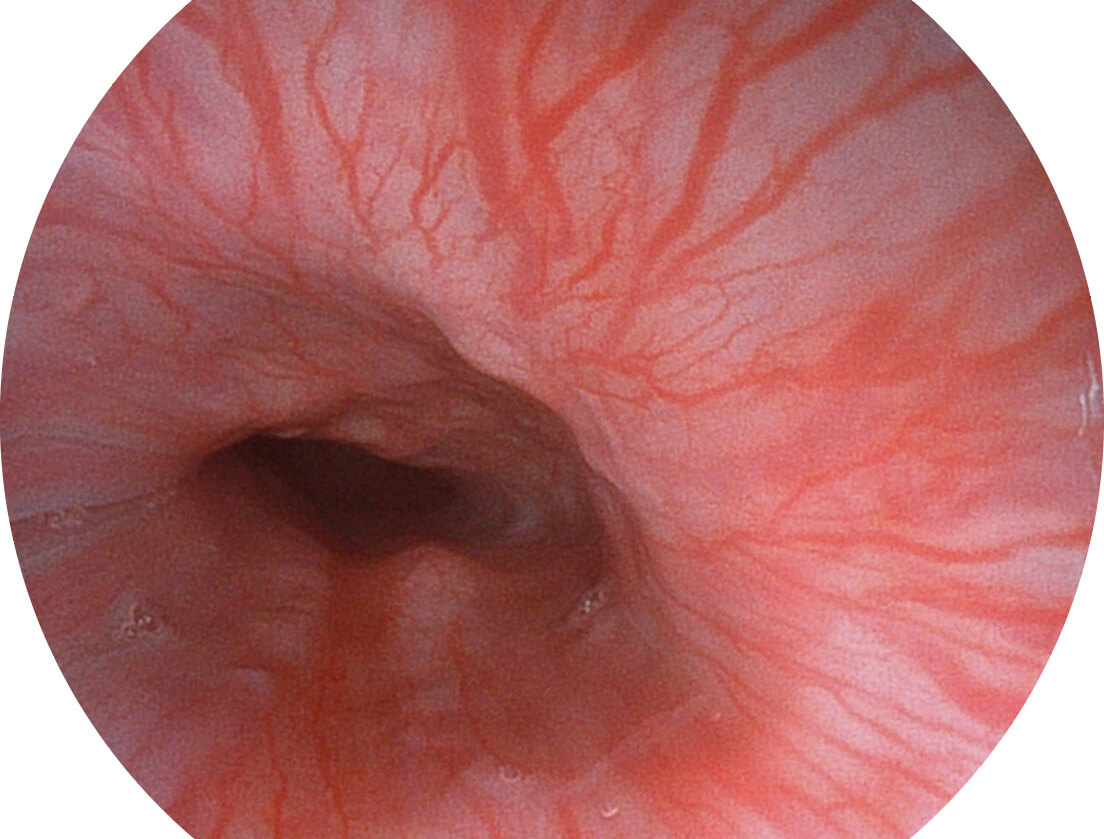

白光图像

VIST图像